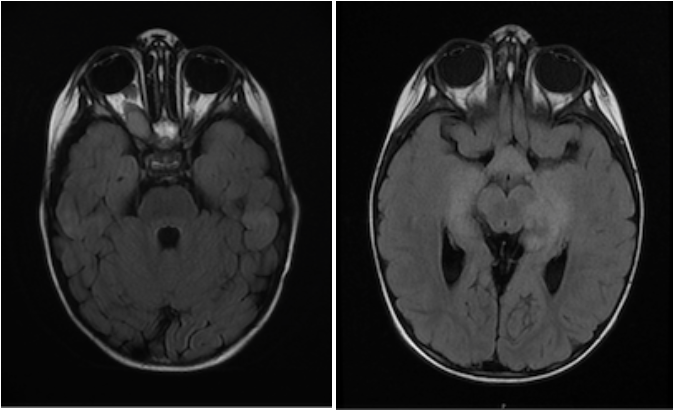

An MRI of the brain with and without contrast demonstrated an extensive optic pathway glioma involving the right optic nerve, optic chiasm/hypothalamus, bilateral optic tracts, and bilateral thalami.

Treatment was initiated with monthly carboplatin/vincristine. Following 3 months of this therapy, MRI brain/orbits demonstrated a mixed response with increased size of the pre-chiasmatic right optic nerve tumor and stable findings elsewhere. Ophthalmologic evaluation showed stability of prior findings. A biopsy was offered, but parents declined due to concern for possible risk of harm to vision. Carboplatin/vincristine therapy was discontinued, and treatment with daily trametinib was begun. However, while still on trametinib monotherapy 12 months later, MRI brain/orbits showed progressive disease with a new left temporal lobe lesion. A biopsy of this lesion was safely performed which revealed a pilocytic astrocytoma, WHO grade 1, with a BRAF-V600E mutation. Dabrafenib was added to the existing trametinib therapy, which resulted in disease stabilization immediately, followed by disease response with tumor shrinkage in all areas.